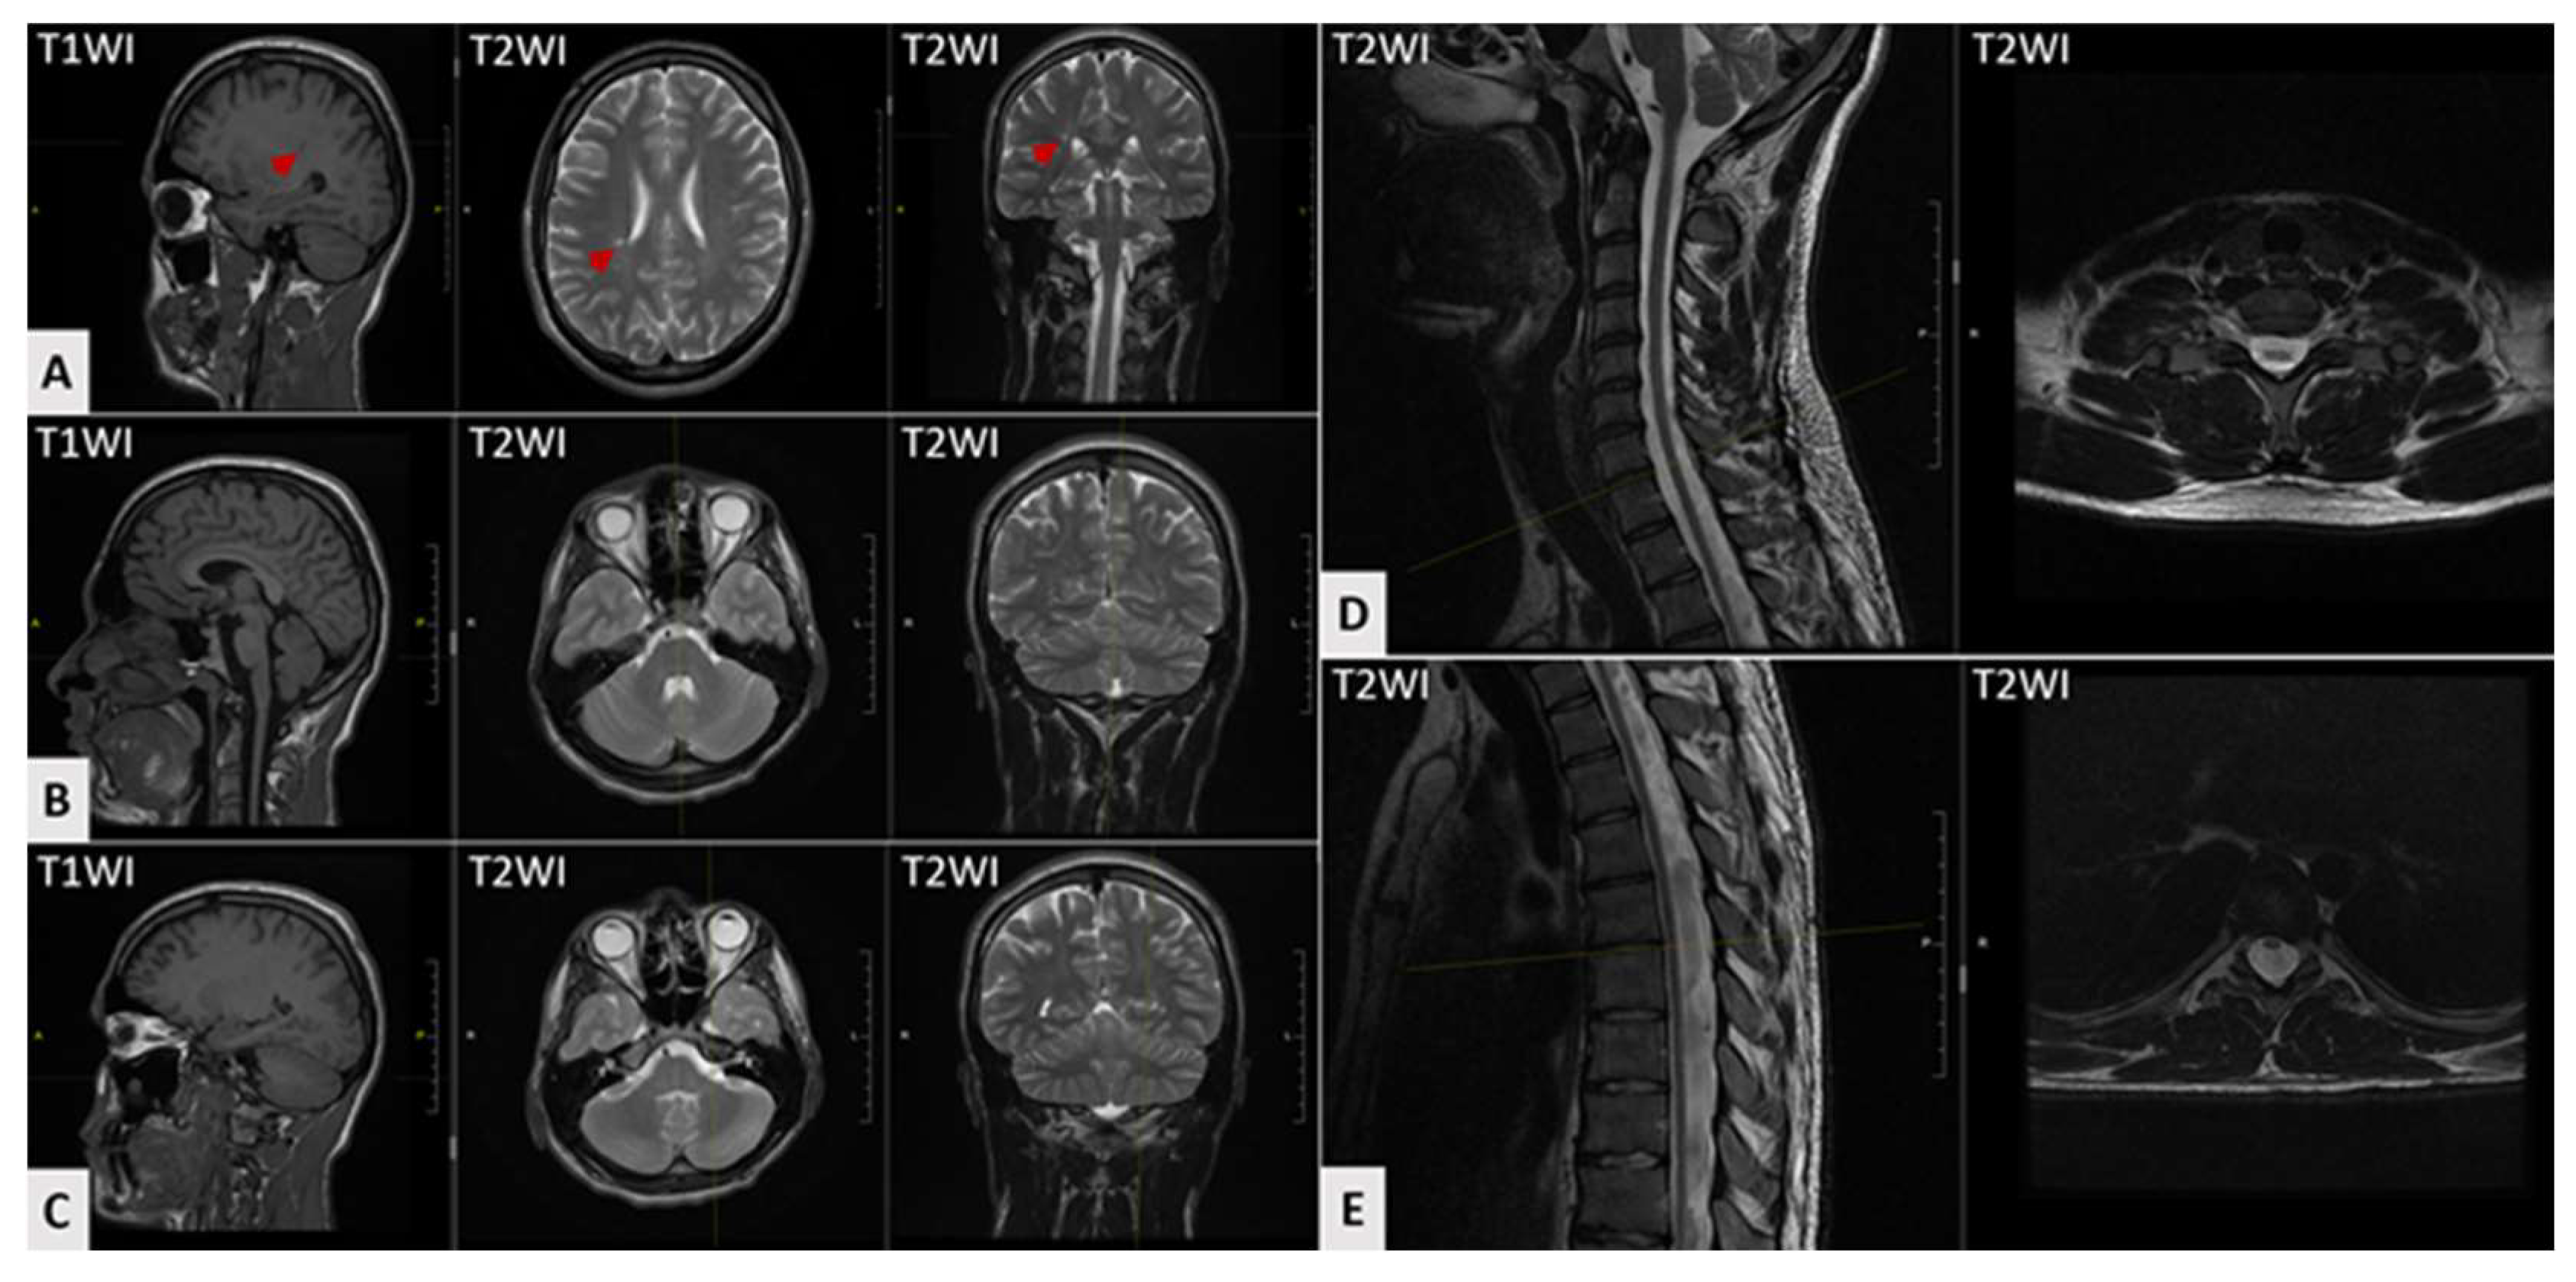

| MRI: cerebral atrophy | 28% (5/18) |

| MRI: cerebellar atrophy | 17% (3/18) |

| MRI: T2-hyperintensities at cerebral white matter | 5% (1/18) |

| MRI: T2-hyperintensities at thalamus | 5% (1/18) |

| MRI: spinal cord atrophy | 44% (8/18) |